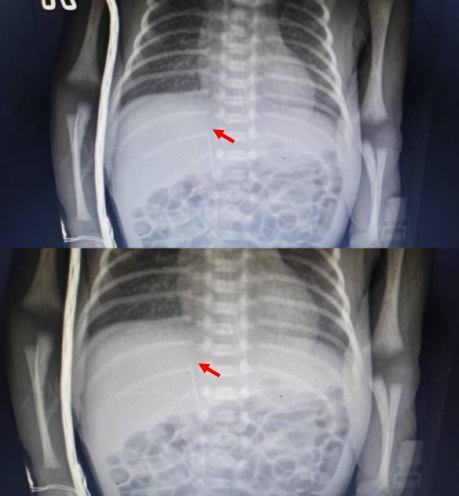

针对四例患儿的特殊病情,新生儿科团队高度重视。术前组织专项病例讨论,结合患儿个体情况,量身定制个性化置管方案与应急预案。操作中,护理人员严格遵循无菌操作原则,凭借娴熟的穿刺技巧顺利完成穿刺、送管,最大程度降低对患儿的刺激。置管后,第一时间拍片确认导管尖端位置,确保管路符合治疗标准。同时,为每例患儿制定专属管路护理计划,加强动态观察与精细化护理,严防并发症发生。